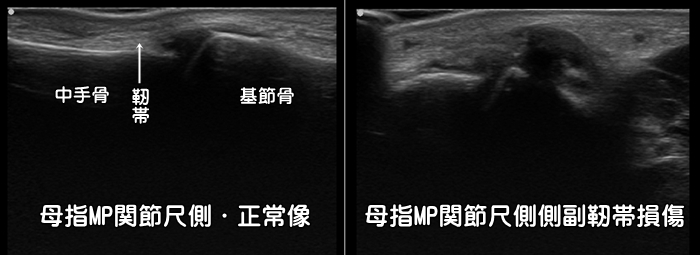

母指MP関節・尺側側副靭帯損傷

親指をついて指が人差し指とは反対側に強く曲げられると、親指の第2関節の靭帯が損傷します。スキーを滑っていて転倒した際にストックが手から離れずに損傷する事が多い事から別名『スキーヤーズ・サム』とも言われます。サム=親指。つまむ際の力が入らなくなったり、関節に不安定性が残存する事もある為に、注意が必要です。